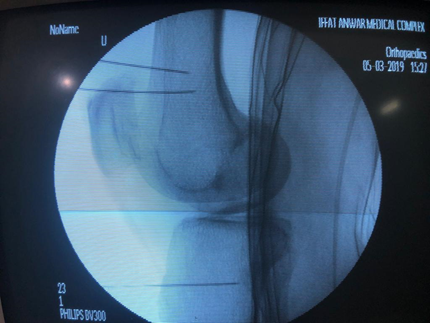

RF Rhizotomies of Genicular Nerves procedure.

RF Needles position in Lateral view.